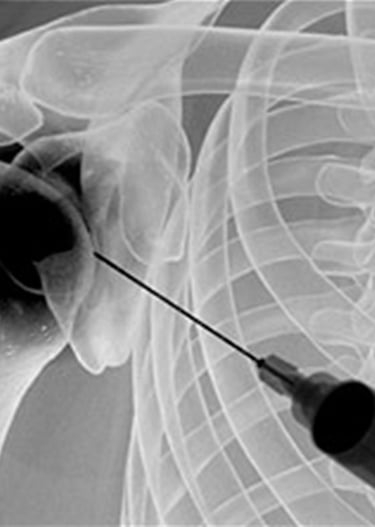

Gydytojas Markas Fiodorovas - ortopedas traumatologas, sporto traumų specialistas, sukaupęs 20 metų patirtį tausojančioje artroskopinėje chirurgijoje. Daugiau nei 650 artroskopinių kelio, peties ir kitų sąnarių operacijų per metus atliekantis chirurgas, taip pat aktyviai įsitraukęs į mokslinę veiklą. Gydytojas yra nuolatinis tarptautinių konferencijų lektorius bei tarptautinis artroskopinės chirurgijos instruktorius.

Gydytojas Markas Fiodorovas - ne tik vienas daugiausiai operuojančių ortopedų - traumatologų Lietuvoje, bet ir aktyvus mokslinės bendruomenės narys, lektorius bei instruktorius. LASTA ir ESKKA asociacijų narys, nuo 2010 metų nuolat skaito pranešimus tarptautinėse konferencijose. Tarptautinis artroskopinės chirurgijos kursų instruktorius nuo 2012m. moko artroskopijos chirurgus visame pasaulyje.